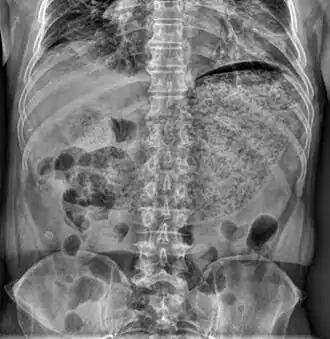

Gastroparese is een vertraagde ontlediging van de maag. Dit is het gevolg van een storing in de bewegingen van de maag. De maagspier trekt te weinig of te onregelmatig samen. Voedsel blijft langer dan normaal in de maag omdat de maag niet regelmatig geleegd wordt. Iemand kan daar erg misselijk van zijn en ook van braken. Een vol gevoel, snelle verzadiging, reflux en maagpijn kunnen nog symptomen zijn.

Het is een functionele stoornis, aan de maag zijn meestal geen afwijkingen te zien, maar de werking is verstoord. Een gastroscopie toont meestal geen letsels aan. Tijdens een maagontledigingsonderzoek kan een vertraagde maaglediging aangetoond worden. Hiervoor dient de patiƫnt een maaltijd (vaak boterhammen met omelet of een pannenkoek) met hierin een kleine hoeveelheid radioactieve stof te eten en wordt gedurende een tweetal uren regelmatig een scintigram van de maag gemaakt. Op die manier kan gevolgd worden hoe lang de testmaaltijd erover doet om te verteren.